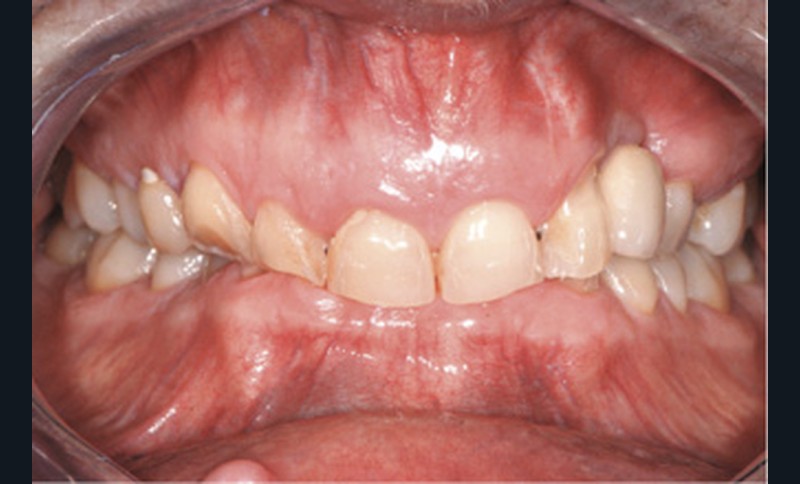

Patiente de 76 ans venue consulter en raison de son inquiétude relative à l’usure de ses dents antérieures mandibulaires très sensibles au froid et générant des difficultés de mastication. La patiente était également désireuse d’améliorer son sourire disgracieux (fig. 1). Pour autant, elle ne souhaitait pas bénéficier d’une restauration d’importance et invasive et refusait catégoriquement toute proposition d’éventuelle orthodontie.